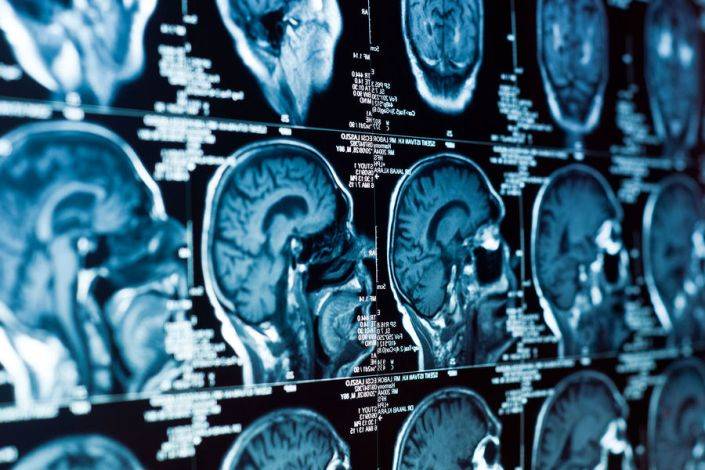

Анализ более 2600 МРТ-сканов мозга людей в возрасте от 30 до 97 лет позволил ученым проследить, как мозг трансформируется с возрастом, и как это соотносится с результатами когнитивных тестов. Выяснилось, что изменения формы мозга происходят неравномерно: одни области сжимаются, другие — расширяются, и у людей с признаками когнитивного снижения эти искажения выражены сильнее.